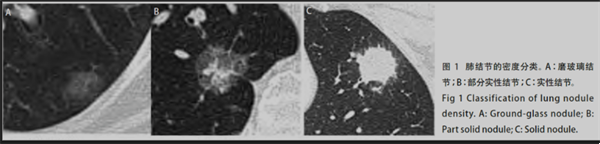

在臨床上,肺結(jié)節(jié)是指肺內(nèi)直徑小于等于3cm的類圓形或不規(guī)則形病灶,影像學(xué)表現(xiàn)為密度增高的陰影,可單發(fā)或多發(fā),邊界清晰或不清晰的病灶。依據(jù)結(jié)節(jié)密度將肺結(jié)節(jié)分為實(shí)性結(jié)節(jié)、部分實(shí)性結(jié)節(jié)和磨玻璃密度結(jié)節(jié)。